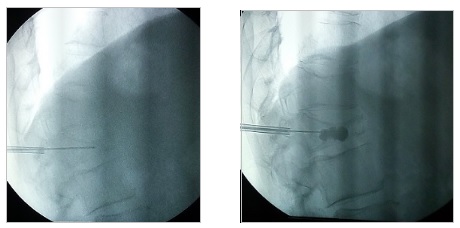

Με τον ασθενή σε πρηνή θέση και υπό τοπική αναισθησία, εισάγεται κάτω από ακτινοσκοπική καθοδήγηση μια βελόνα που διέρχεται από το πλάγιο τμήμα του πρώτου οσφυϊκού σπονδύλου, το άκρο της οποίας στην τελική του θέση φθάνει στην περιοχή ακριβώς μπροστά από την αορτή. Γίνεται έγχυση σκιαγραφικού για απεικόνιση του πλέγματος και αμέσως μετά δίνεται το τοπικό αναισθητικό και η κορτιζόνη. Μέσω της διαδικασίας αυτής μπορούν να εγχυθούν και νευρολυτικοί παράγοντες, όπως η αλκοόλη και η φαινόλη, οι οποίοι έχουν καταστροφική δράση. Το block με τοπικό αναισθητικό και κορτιζόνη έχει δράση για λίγες μέρες. Όσοι ασθενείς ανταποκριθούν θετικά, μπορούν να υποβληθούν σε δεύτερο χρόνο σε νευρόλυση με χρήση ραδιοσυχνοτήτων, η οποία προσφέρει μακρά θεραπευτική δράση.